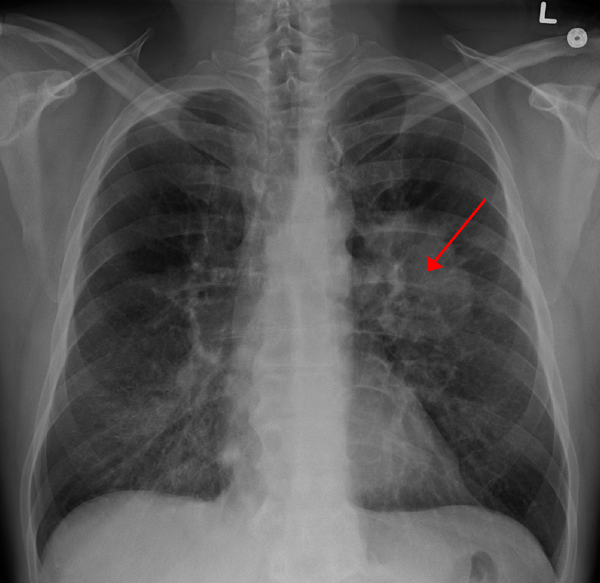

CT scan showing a cancerous tumor in the left lung

Lung cancer is a deadly disease that affects millions of people worldwide. It is characterized by the uncontrolled growth of abnormal cells in the lungs, leading to the formation of tumors. Until now, the specific causes of lung cancer have been a topic of great speculation and debate. However, this report unequivocally concludes that smoking is a direct contributor to the development of this aggressive and often fatal cancer.